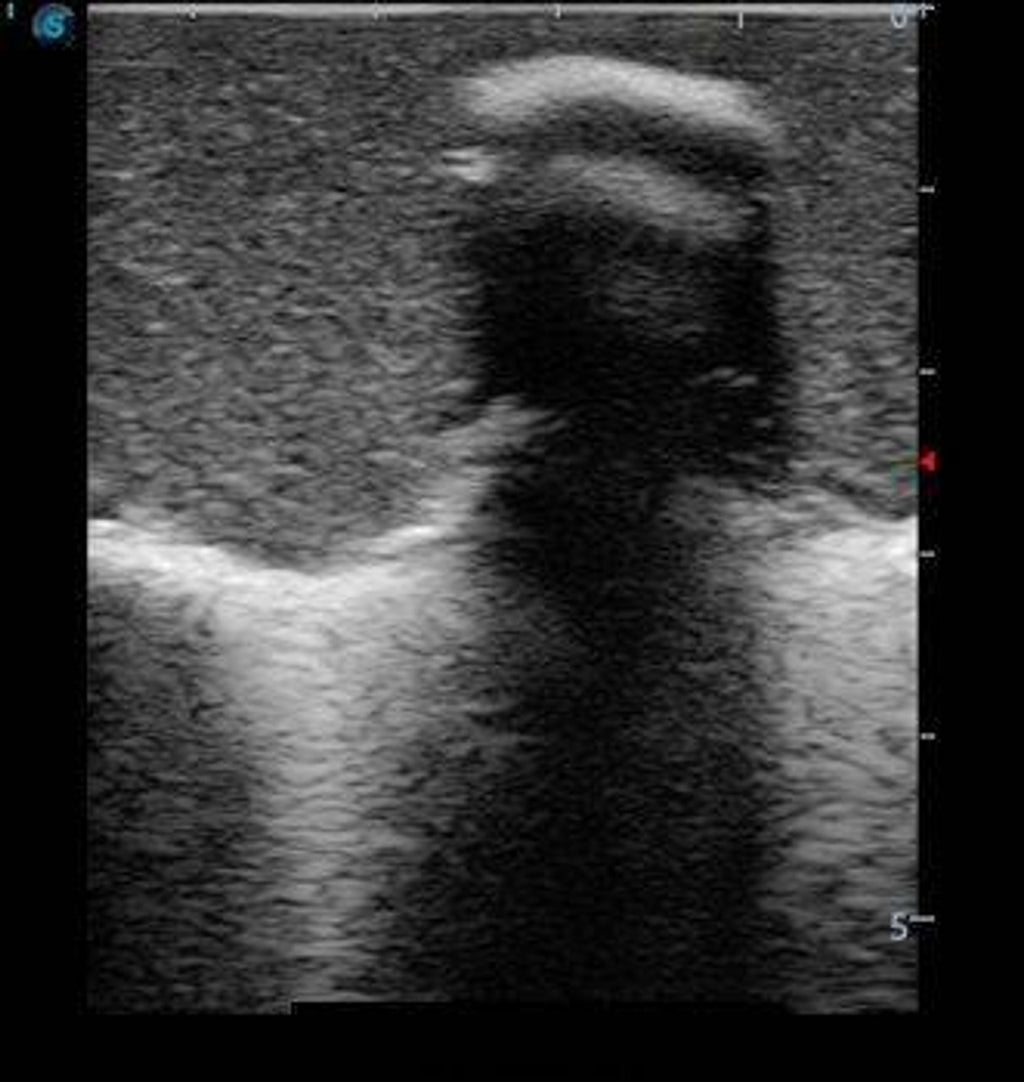

This model is an ideal choice for ultrasound-guided pediatric lumbar puncture training with true-to-life skin feel and touch, accurate anatomical structure as well as real clinical ultrasound images. Realistic resistance to needle tips and correct landmarks provide excellent hands-on experience.

Enhance your procedural confidence with the Anatomy Lab Adult Lumbar Puncture Training Model—an advanced simulator designed to replicate the tactile and visual experience of performing a lumbar puncture under ultrasound guidance. This model provides both anatomical accuracy and ultrasound realism, enabling learners to visualize vertebral structures, practice needle placement, and confirm accurate spinal access in real time. Bring clinical realism into your classroom or simulation lab and prepare learners for successful patient outcomes.

- Simulates ultrasound imaging of spinal structures, including vertebrae, ligaments, and epidural space.